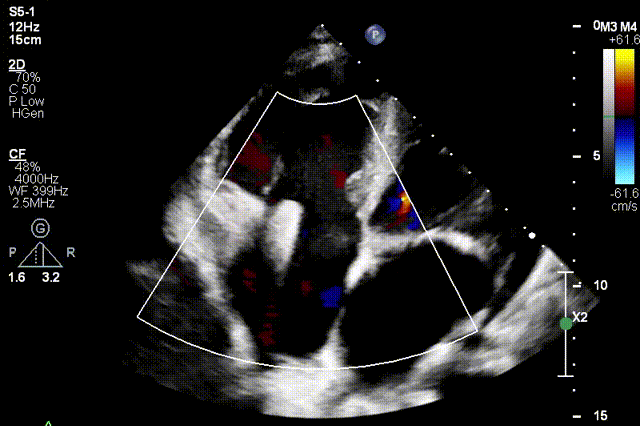

术前超声

术后超声